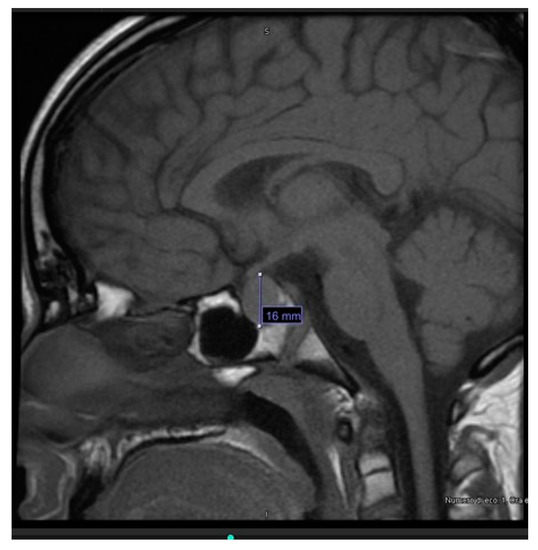

The US of thyroid and edematous soft tissues showed an enlarged thyroid gland, with heterogeneous echo structure, multiple hypoechoic foci, micronodular appearance and increased vascularization (consistent with thyroiditis), and thickening of subcutaneous adipose tissue, respectively (Figure 1A–C).

Figure 1. Ultrasound findings of thyroiditis (A), thickening and hyperechogenic of subcutaneous adipose tissue in the right supraclavicular region (B) and in the right armpit (C).